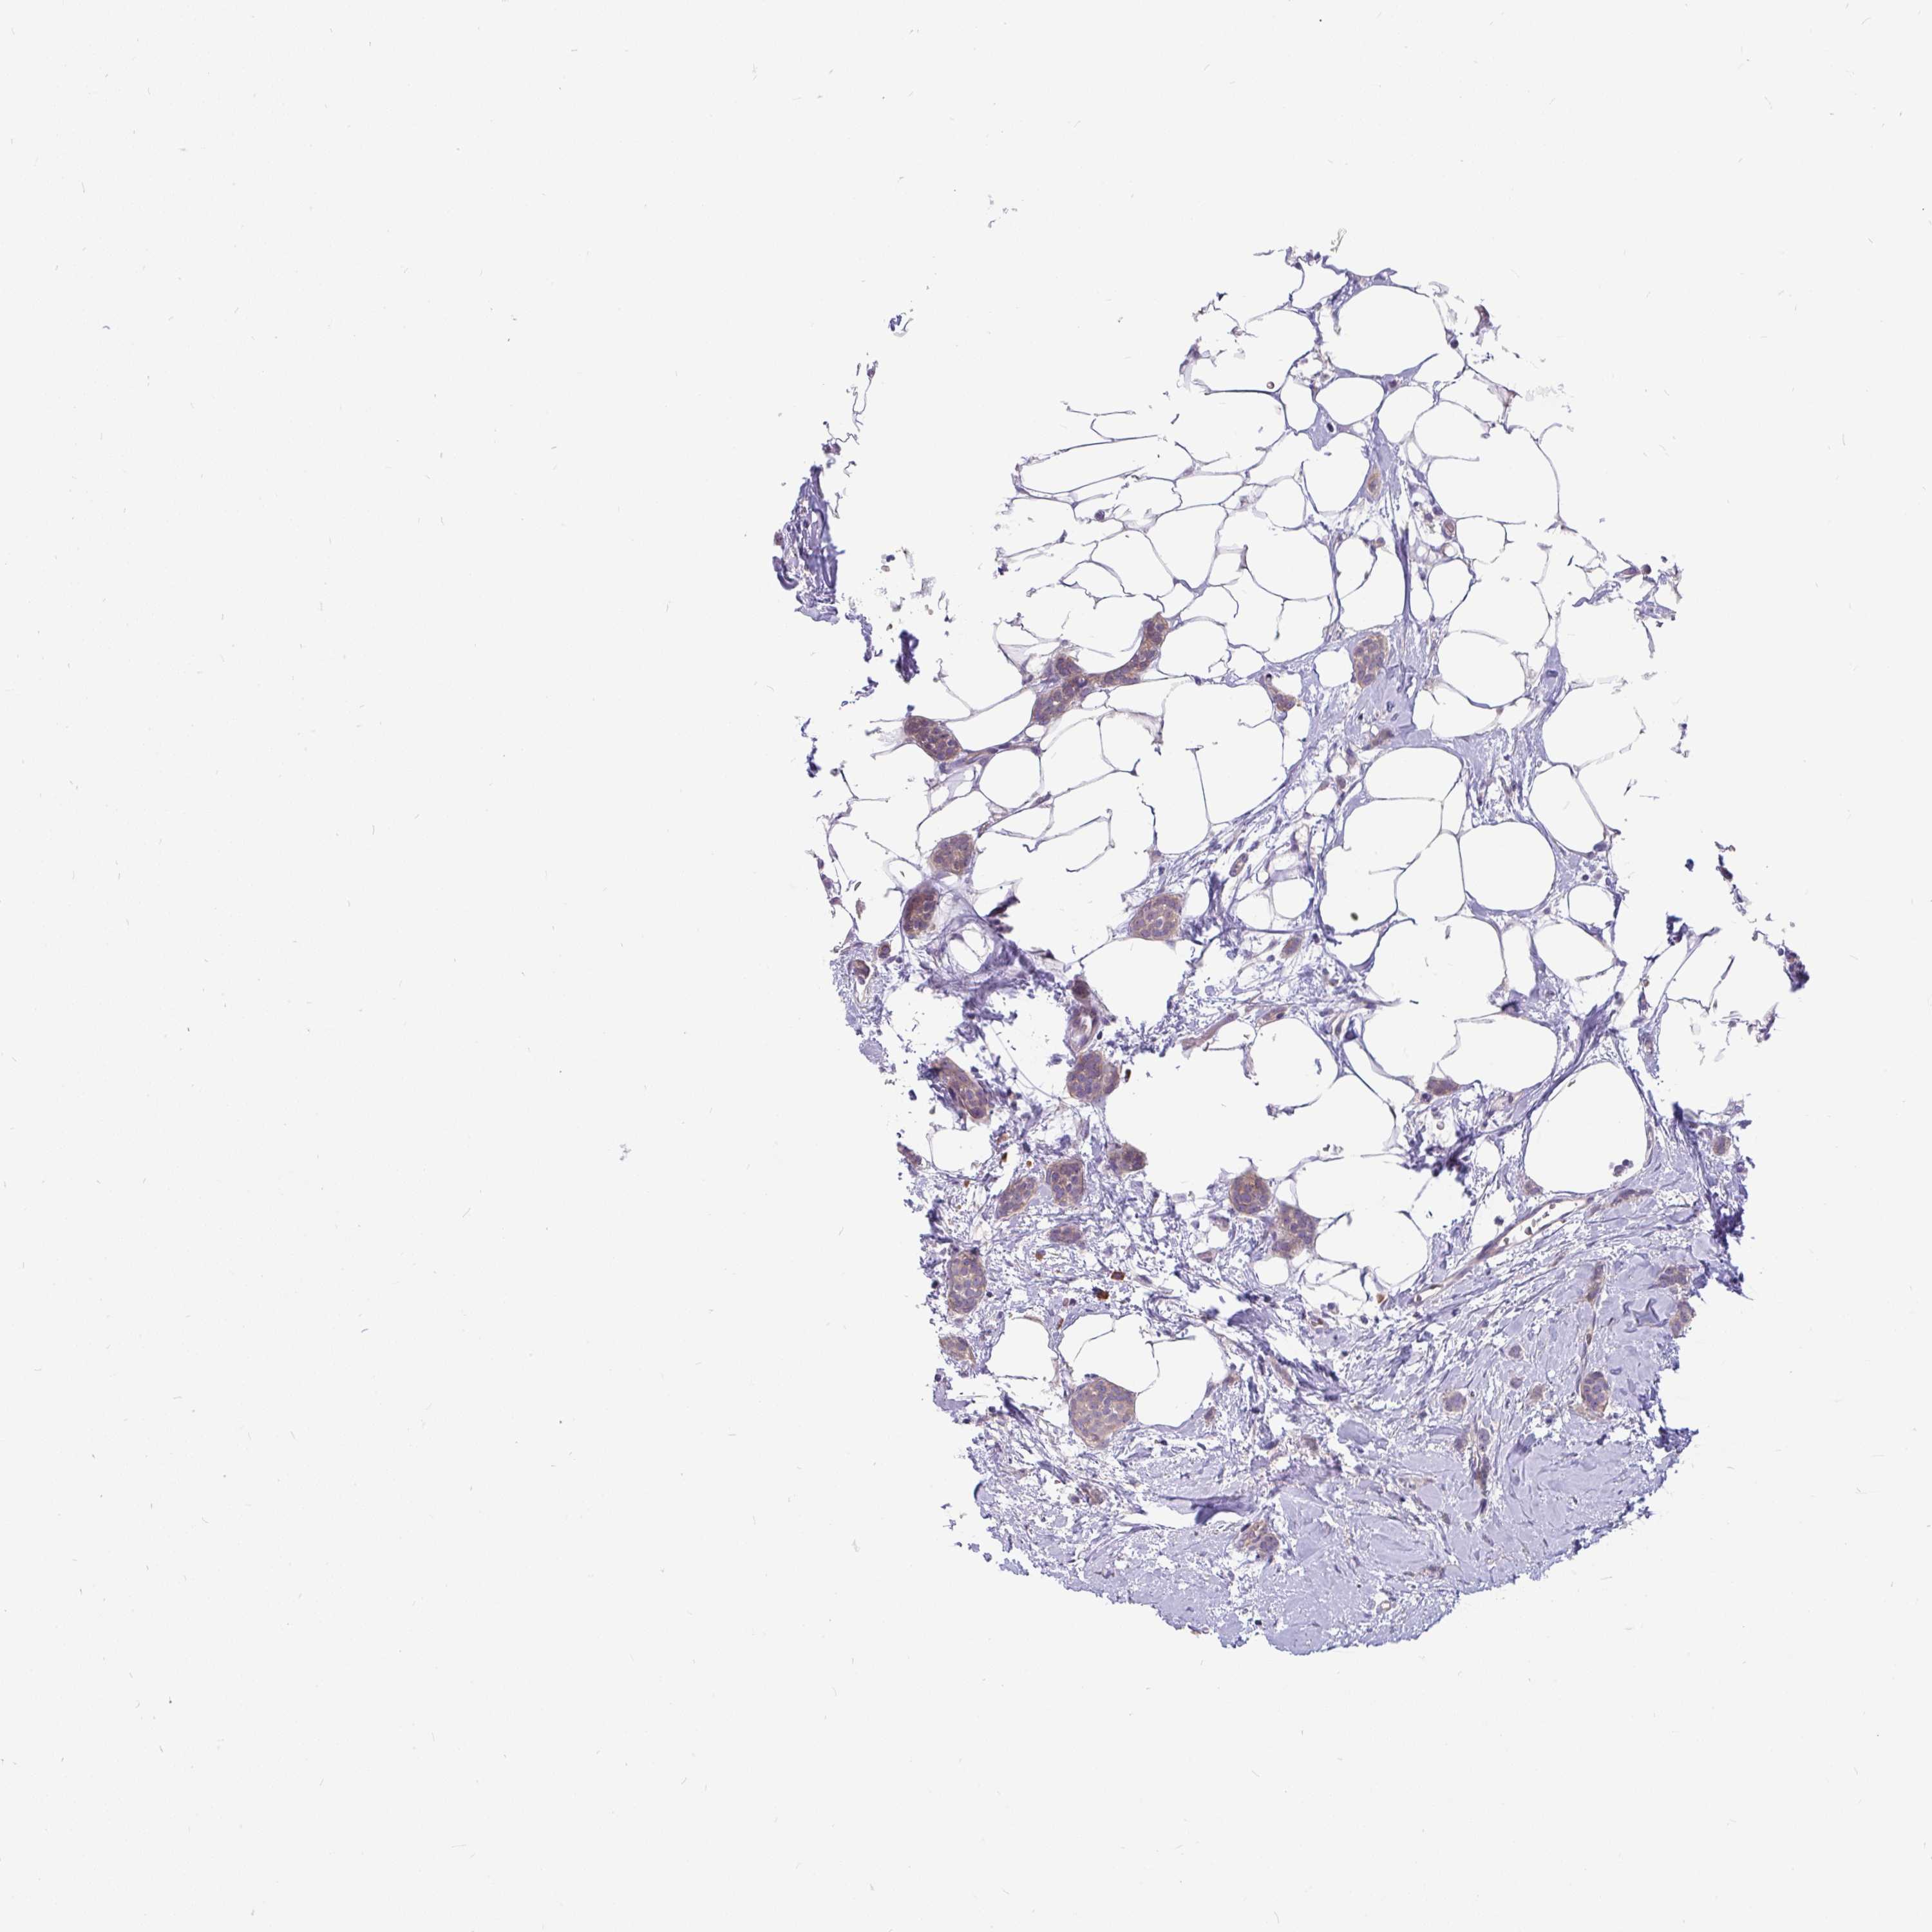

CANCER BREAST CANCER Show tissue menu

BRCA TCGA BRCA VALIDATION PROTEIN EXPRESSION